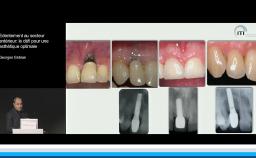

La présentation s’attache à détailler en quoi l’implantation en zone esthétique constitue un challenge lorsqu’il s’agit de réhabiliter la fonction sans oublier de rétablir l’esthétique. A travers quelques cas cliniques, le Dr Eycken s’appuie sur la classification SAC de l’ITI pour évaluer la complexité du cas et y apporter la solution thérapeutique adaptée. Il revient également sur l’importance du positionnement de l’implant dans les 3 sens de l’espace et sur la qualité des tissus mous environnants.